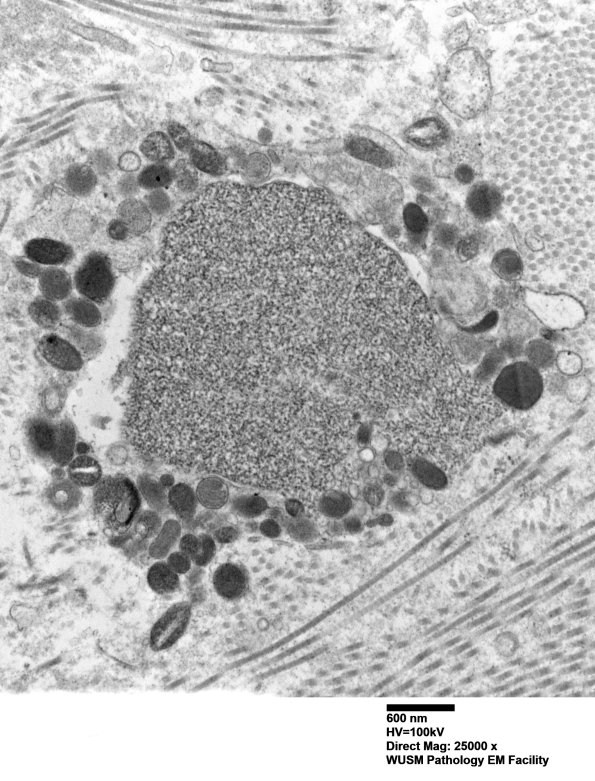

Higher magnification of image #12E3. (electron micrograph)